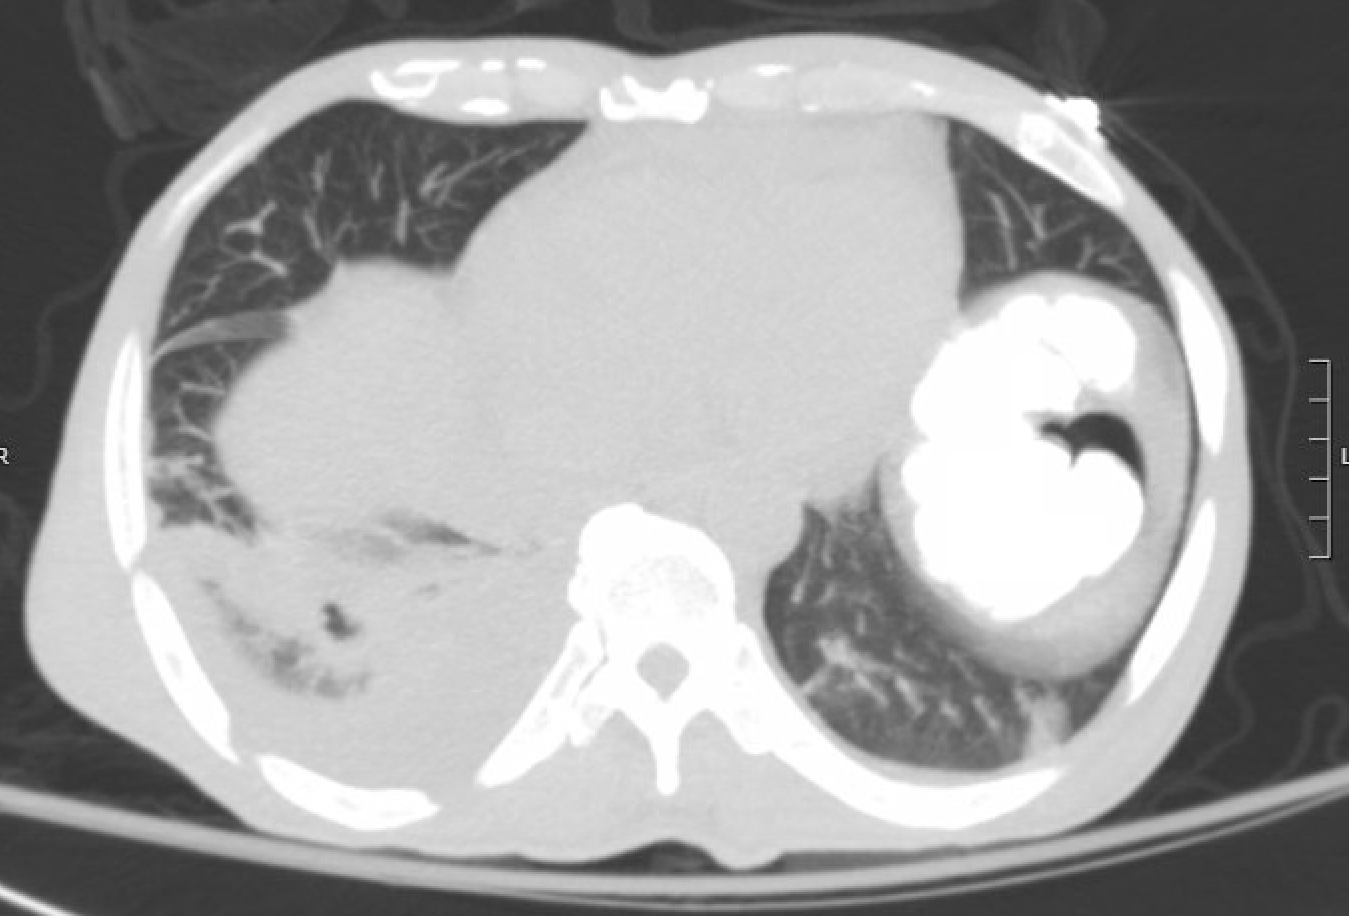

IMAGE 1: Cavitation in Right Lower Lobe on Repeat Chest CT

Case Presentation: A 57-year-old Honduran male with no past medical history presented with two weeks of recurrent fevers, dyspnea, bilateral blurred vision, and pain in his low back, flank, and abdomen. Chest X-ray revealed a round opacity over the right lower lung. CT chest, abdomen, and pelvis showed patchy consolidation in the right lower lobe (RLL), bilateral pleural effusions, and perinephric stranding. He was admitted for hypoxemia with suspected community acquired pneumonia. Ophthalmology noted xerophthalmia and bilateral retinal detachments, prompting an ANA and Quantiferon, both of which were positive. Follow-up labs were significant for ESR 125, CRP 9, C3 of 39 (low), undetectable C4. Sputum and pleural fluid tuberculosis (TB) PCR and AFB smears were negative. Subsequent CTA of the chest revealed RLL pulmonary embolism and thrombosis of the left internal jugular and brachiocephalic veins.Laboratory findings led to consultation with Infectious Disease (ID) and Rheumatology. ID did not favor TB as the primary diagnosis given the patient’s paucity of risk factors with negative PCR and AFB smears. A lymph node biopsy was also unrevealing. Rheumatology noted his presentation was atypical for a sentinel episode of systemic lupus erythematosus (SLE); however, after anti-Smith, anti-dsDNA, RNP, and SSA antibodies were positive and the patient had new onset pericardial effusion the decision was made to initiate both systemic corticosteroids for SLE and rifampin for latent TB. After 16 days on 20mg prednisone, the patient then developed an unstable arrhythmia and repeat CT angiography showed a cavitary pulmonary lesion, raising concern for transformation from latent to active TB. He was transitioned to RIPE therapy and discharged to home four days later. Outpatient renal biopsy confirmed lupus nephritis and a later thoracentesis confirmed active tuberculosis.